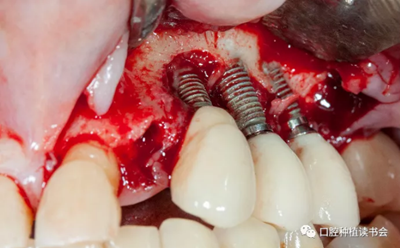

首先去除了螺絲固位的牙冠,引流膿液,翻全厚瓣暴露受感染部位的種植體。對(duì)暴露種植體進(jìn)行種植體成形術(shù),金剛砂車針磨除種植體表面凹槽(圖 20)。

圖20 種植體周圍有膿液滲出,翻瓣后行種植體成形術(shù)